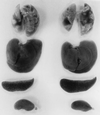

129sv mice functionally deleted of the antimicrobial resistance gene, Nramp1, were found to be as resistant as wild-type mice to infection with the virulent H37Rv strain of Mycobacterium tuberculosis, as determined by monitoring bacterial growth in major organs and recording host survival times. Death of infected mice of both types was associated with extensive infection-induced pathology in the lungs but not in other major organs. These findings are in keeping with the view that Nramp1 is of limited importance in resistance to tuberculosis in mice.